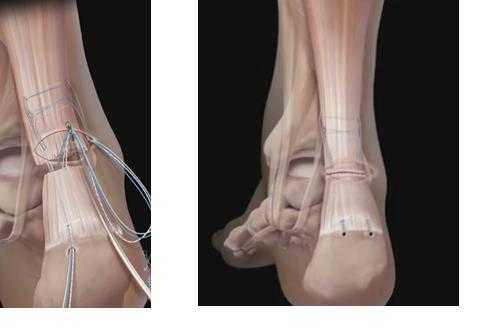

Далее выполняем двурядный шов ахиллова сухожилия при помощи якорных фиксаторов Swive-lock. При этом дистальный конец сухожилия площадью 2\2 см плотно прижимается к губчатому веществу пяточной кости.

Данный тип фиксации настолько надёжен, что после рефиксации свежих разрывов, или открытого лечения инсерционного тендинита и деформации Хаглунда, дозированную нагрузку на конечность можно давать уже через 2 недели после операции! В случае застарелого разрыва, из-за того, что была выполнена удлиняющая тенопластика, нагрузка даётся по стандартной схеме через 6 недель.

В результате операции мы получаем адекватно натянутое ахиллово сухожилие, надёжно фиксированное к пяточной кости при помощи 4 анкерных фиксаторов по методике Arthrex Speed Bridge.